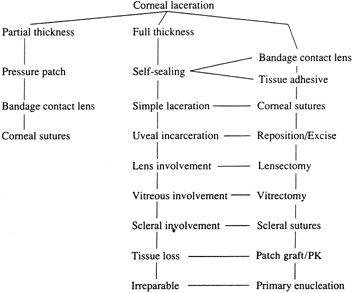

With surgical repair of corneoscleral lacerations, the primary goal is to achieve a watertight globe and maintain structural integrity. Secondary goals include removing any disrupted lens fragments and vitreous, repositioning any uveal tissue, relieving vitreous incarceration, removing any intraocular foreign bodies, and restoring normal anatomic relationships. A methodic surgical strategy is essential for injury repair. Such a stepwise schema affords the surgeon a standard and reproducible approach to the protean manifestations of penetrating anterior segment trauma (Fig. 1).

|